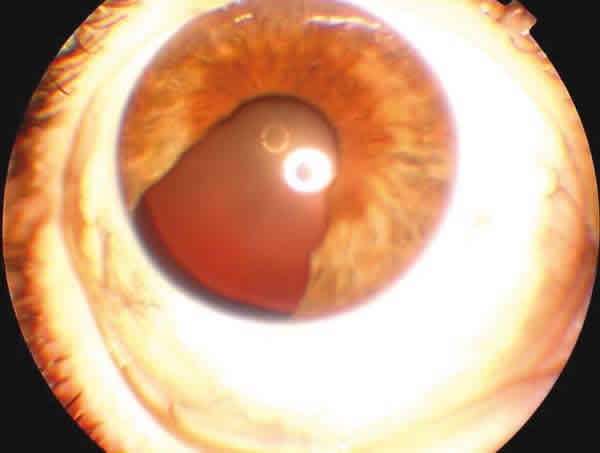

En la exploración oftalmológica se evidenció una agudeza visual corregida de 0,2 en ambos ojos, sin mejoría con agujero estenopeico. A la lámpara de hendidura se observó una masa iridiana pigmentada en el cuadrante temporal inferior que no invadía el ángulo iridocorneal (fig. 1). En la oftalmoscopía se encontró una hipoplasia macular en ambos ojos.

Fig. 1.